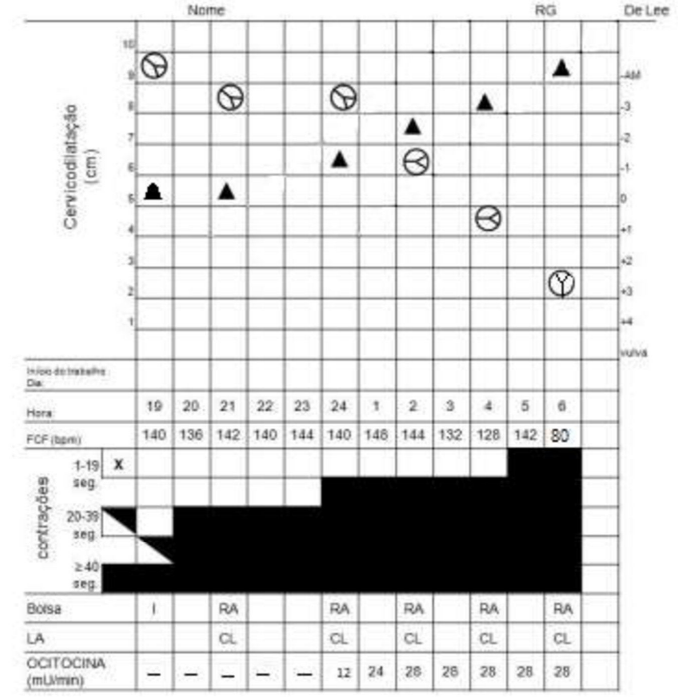

Gestante 35 anos de idade, primigesta e na 39ª semana de gravidez. Na emergência obstétrica, queixou-se de dor em baixo ventre. Ao exame, batimentos cardiofetais de 140 bpm, dinâmica uterina de 2 contrações / 10 minutos / 35 e 45 segundos. Ao toque vaginal, encontrava-se com 5 cm de dilatação, 80% de esvaecimento cervical, bolsa das águas íntegras e cefálico. Observe o partograma abaixo:

Assinale a alternativa que indica a estrutura anatômica menos relevante sobre o mecanismo do parto dessa paciente.